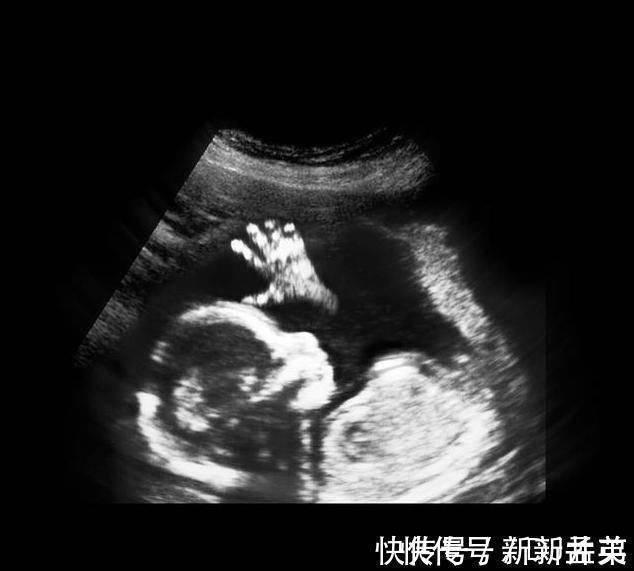

进入了16周,胎儿具备了很多本领,比如吞咽羊水、排出尿液、玩耍脐带、开始有了妈妈能够感受到的胎动,胎儿生殖器官的发育开始可见。

其实从孕9周开始,胎儿的性别就开始分化,孕17周,B超扫描清晰可见胎儿的性别,不过也有的宝宝因为胎位的原因,或者脐带遮挡,让医生产生了误判,男女会出现翻盘的可能呢。